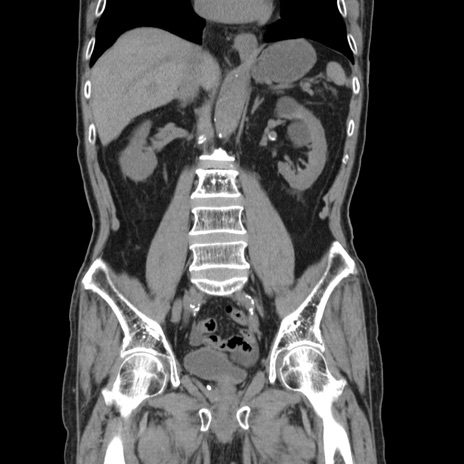

症例24(冠状断像)

【症例】80歳代男性

【主訴】左側腹部痛、嘔吐

【現病歴】本日早朝より左腹部に痛みあり。昼頃嘔吐認めたため、救急要請。

【既往歴】直腸癌(Mile手術)、胆摘

【身体所見】意識清明、BT 35.9℃、BP 221/93mmHg、SpO2 97%(RA) 、腹部:左ストーマ周囲に限局性の腹部膨隆あり。 膨隆部自発痛・圧痛あり・軟。

【データ】WBC 7700、CRP 0.09